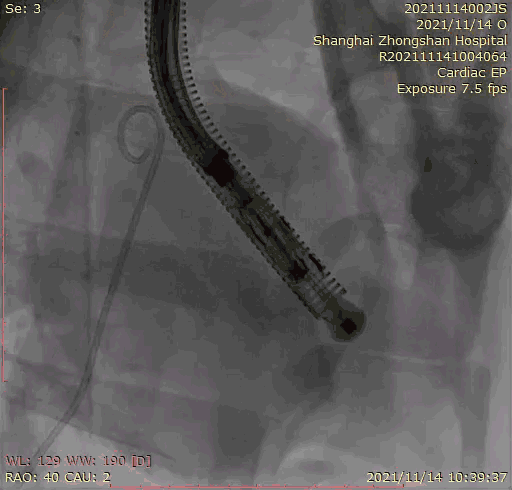

本次临床前研究经右侧颈静脉置入LuX-Valve Plus输送系统可调弯鞘管,在DSA及超声引导下将人工三尖瓣瓣膜植入到原有三尖瓣位置,利用独特的锚定技术将人工瓣膜支架可靠固定在预定的位置。